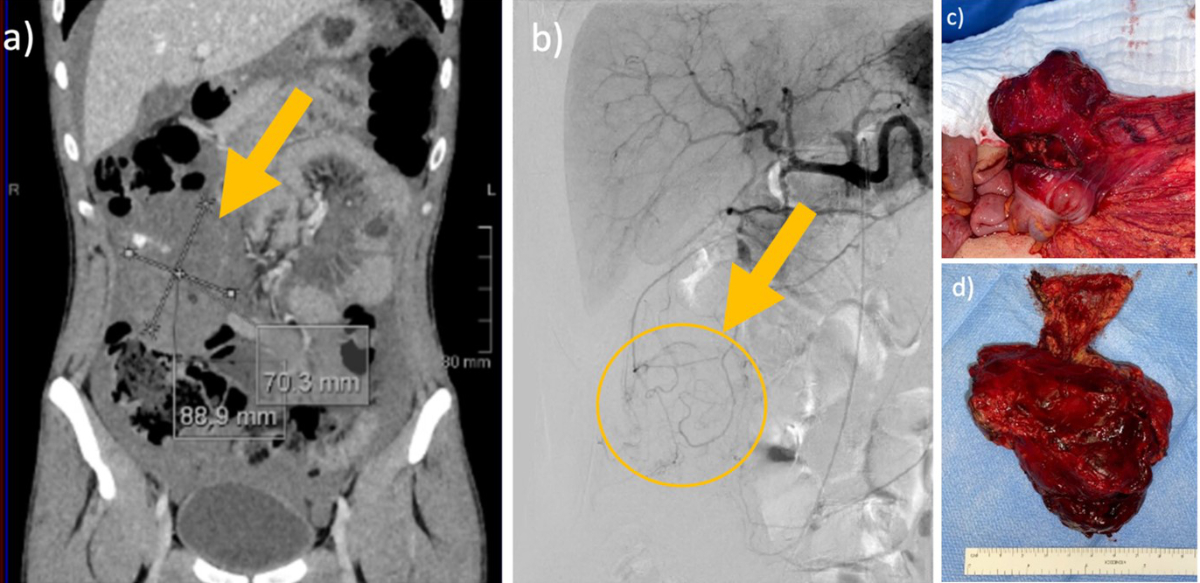

A 25-year old male patient with moderate hemophilia B and progressive abdominal pain was admitted to our emergency department. The initial hemoglobin was 65 g/l. The abdominal CT scan detected ubiquitous intraabdominal free fluid and a tumor in the right hemiabdomen (figure 3). The exploratory laparotomy presented non-coagulated blood in all four quadrants and a coagulum-like tumor in the omentum majus attached to the right colon. Complete resection followed. Histology revealed a hemophilic pseudotumor (13 × 8 × 6 cm). The postoperative course and 3 months follow-up was uneventful.

Figure 3Intraabdominal pseudotumour in a 25-year-old male patient.

25-year-old male patient with moderate haemophilia B with progressive abdominal pain and a haemoglobin of 65 g/l. Abdominal CT scan detected ubiquitous intraabdominal free fluid and a tumour in the right hemiabdomen. Exploratory laparotomy presented non-coagulated blood in all four quadrants and a coagulum-like tumour in the omentum majus attached to the right colon. Complete resection followed. Histology revealed a haemophilic pseudotumour (13 × 8 × 6 cm).Postoperative course and three-month follow-up were uneventful.

(a) Contrast CT venous phase with tumour 6.6 × 7.4 × 9.6 cm, (b) Angiography with no sign of active bleeding, (c) Intraoperative finding, (d) Resected specimen